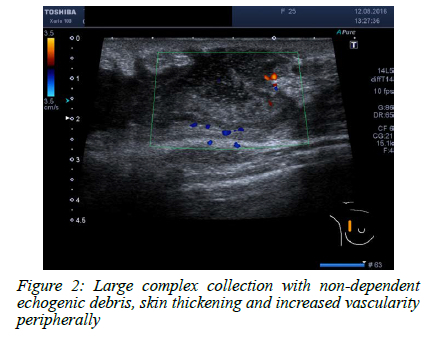

In nodular TB, an ultrasound scan often reveals a well-defined oval hypoechoic mass with posterior acoustic enhancement (Figure 1). The ultrasound picture may resemble a fibroadenoma. These hypoechoic lesions demonstrate no vascularity but rather a fluid collection containing debris. Ultrasound-guided aspiration of purulent fluid distinguishes these lesions from solid breast masses. In the sclerosing form, textural change with no visible fluid may mimic inflammatory carcinoma. The disseminated form of TB is associated with multiple anechoic collections, with and without debris, scattered throughout the breast with or without associated fistulation to the skin (Figure 2). Axillary lymphadenopathy is a common finding in breast TB; lymph nodes can show a spectrum of cortical thickening, solid or necrotic lymph nodes (Figure 3).2025